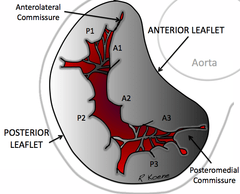

Structure

The mitral valve is typically 4–6 cm² in area. It has two cusps, or leaflets (the anteromedial leaflet and the posterolateral leaflet), that guard the opening. The opening is surrounded by a fibrous ring known as the mitral valve annulus. (The orientation of the two leaflets resembles a bishop's mitre, whence the valve receives its name.[1]) The anterior cusp protects approximately two-thirds of the valve (imagine a crescent moon within the circle, where the crescent represents the posterior cusp). Although the anterior leaflet takes up a larger part of the ring and rises higher, the posterior leaflet has a larger surface area. These valve leaflets are prevented from prolapsing into the left atrium by the action of chordae tendineae, the tendons attached to the posterior surface of the valve.

The inelastic chordae tendineae are attached at one end to the papillary muscles and at the other to the valve cusps. Papillary muscles are finger-like projections from the wall of the left ventricle. Chordae tendineae from each muscle are attached to both leaflets of the mitral valve. Thus, when the left ventricle contracts, the intraventricular pressure forces the valve to close, while the tendons keep the leaflets coapting together and prevent the valve from opening in the wrong direction (thus preventing blood to flow back to the left atrium). Each chord has a different thickness. The thinnest ones are attached to the free leaflet margin, whereas thickest ones (strut chords) are attached quite away from the free margin. This disposition has important effects on systolic stress distribution physiology [2]